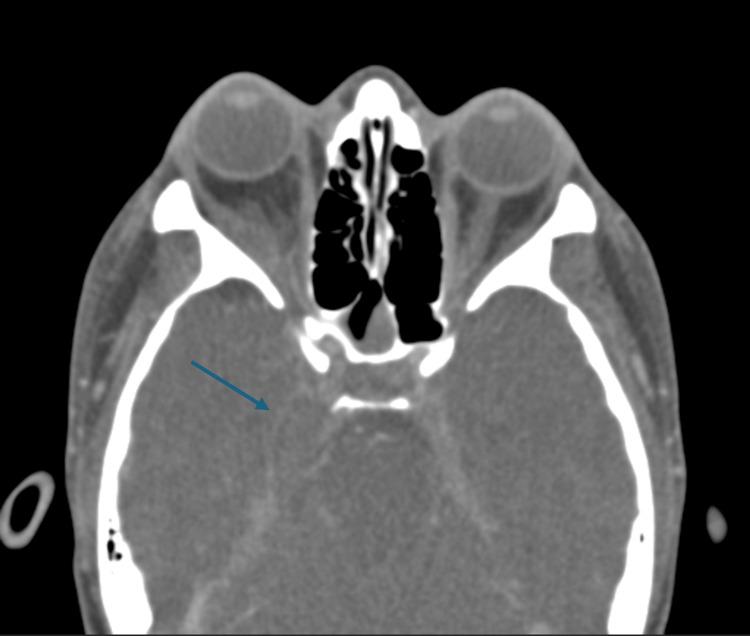

Orbital cellulitis is a serious infection that can lead to severe complications if not promptly diagnosed and treated. This case report describes an unusual presentation of bilateral orbital cellulitis in a previously healthy 29-year-old female, complicated by cerebral vein thrombosis and meningitis. The patient's young age and lack of significant medical history make this case particularly noteworthy. Initially presenting with a local infection over the right nose that rapidly progressed to bilateral orbital cellulitis, subsequent imaging revealed extensive complications including bilateral cavernous sinus thrombosis, sphenoid sinusitis, and intracranial abscesses. Blood cultures were positive for methicillin-resistant Staphylococcus aureus (MRSA), an uncommon finding in community-acquired orbital cellulitis. The patient underwent sinus endoscopy and bilateral sphenoidotomy, followed by a prolonged course of intravenous and oral antibiotics. This case highlights the potential for severe complications in orbital cellulitis, even in young, healthy individuals, and emphasizes the importance of prompt, aggressive treatment and multidisciplinary management. It is imperative for clinicians to maintain a high index of suspicion for atypical pathogens and rare complications in seemingly routine cases.

眼眶蜂窝织炎是一种严重的感染,如果不及时诊断和治疗,可能会导致严重的并发症。本病例报告描述了一名既往健康的29岁女性双侧眼眶蜂窝织炎的不寻常表现,并伴有脑静脉血栓形成和脑膜炎。患者年轻且无重大病史,使得该病例尤为值得关注。最初表现为右鼻局部感染,迅速发展为双侧眼眶蜂窝织炎,随后的影像学检查显示出广泛的并发症,包括双侧海绵窦血栓形成、蝶窦炎和颅内脓肿。血培养结果显示耐甲氧西林金黄色葡萄球菌(MRSA)呈阳性,这在社区获得性眼眶蜂窝织炎中并不常见。患者接受了鼻窦内窥镜检查和双侧蝶窦切开术,随后进行了长时间的静脉和口服抗生素治疗。本病例强调了眼眶蜂窝织炎即使在年轻健康个体中也可能出现严重并发症的可能性,并强调了及时、积极治疗和多学科管理的重要性。临床医生必须在看似常规的病例中对非典型病原体和罕见并发症保持高度的怀疑指数。